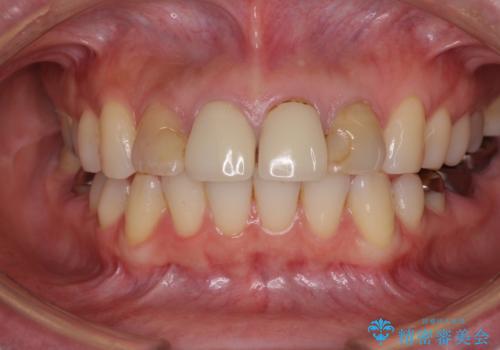

- 前歯のクラウンの変色や歯の変色を気にして来院された患者様です。

グラスファイバーを用いた土台により歯質を強化した上で、オールセラミッククラウンにて補綴することとしました。